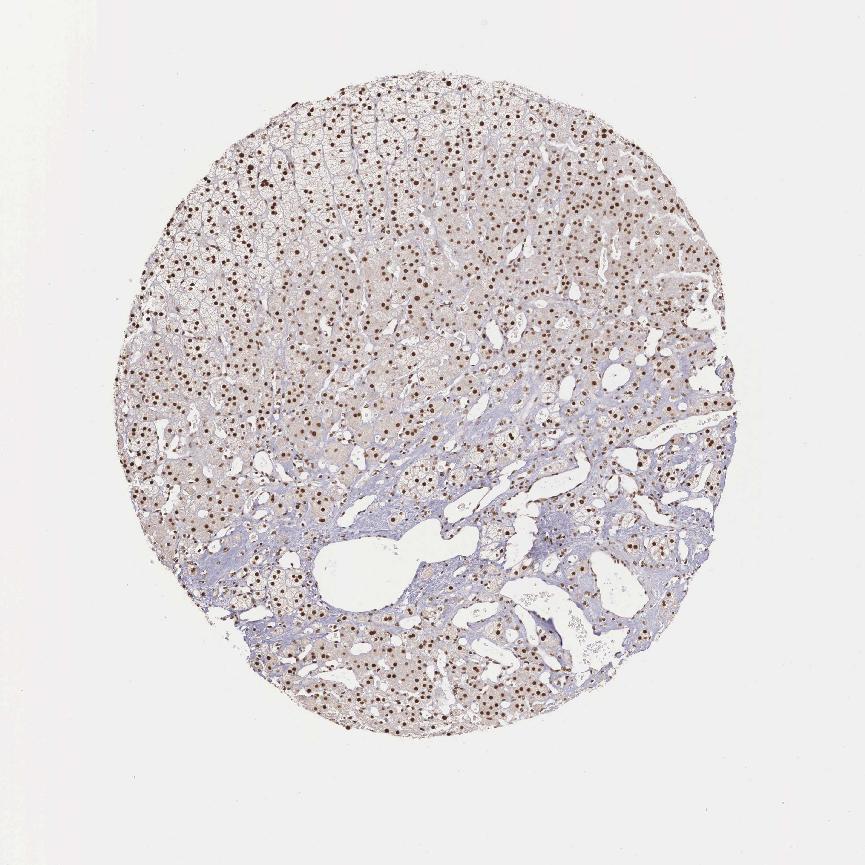

ADRENAL GLAND - Antibody stainingi

Antibody staining in the annotated cell types in the current human tissue is reported as not detected, low, medium, or high, based on conventional immunohistochemistry profiling in selected tissues. This score is based on the combination of the staining intensity and fraction of stained cells.

Each image is clickable and will lead to virtual microscopy that enables deeper exploration of all samples and also displays staining intensity scores, fraction scores and subcellular localization as well as patient and tissue information for each sample.

Antibody HPA000827Antibody CAB009882

Glandular cells HighHigh